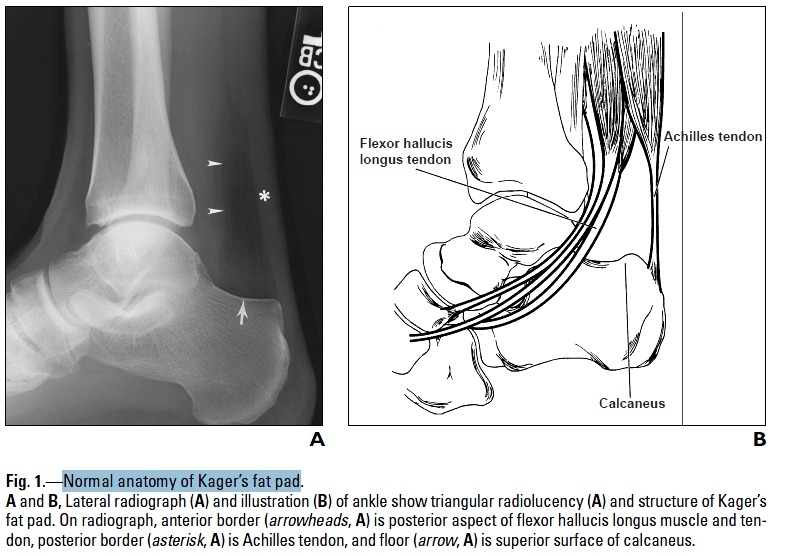

- Kager's fat pad = pre-achilles triangle